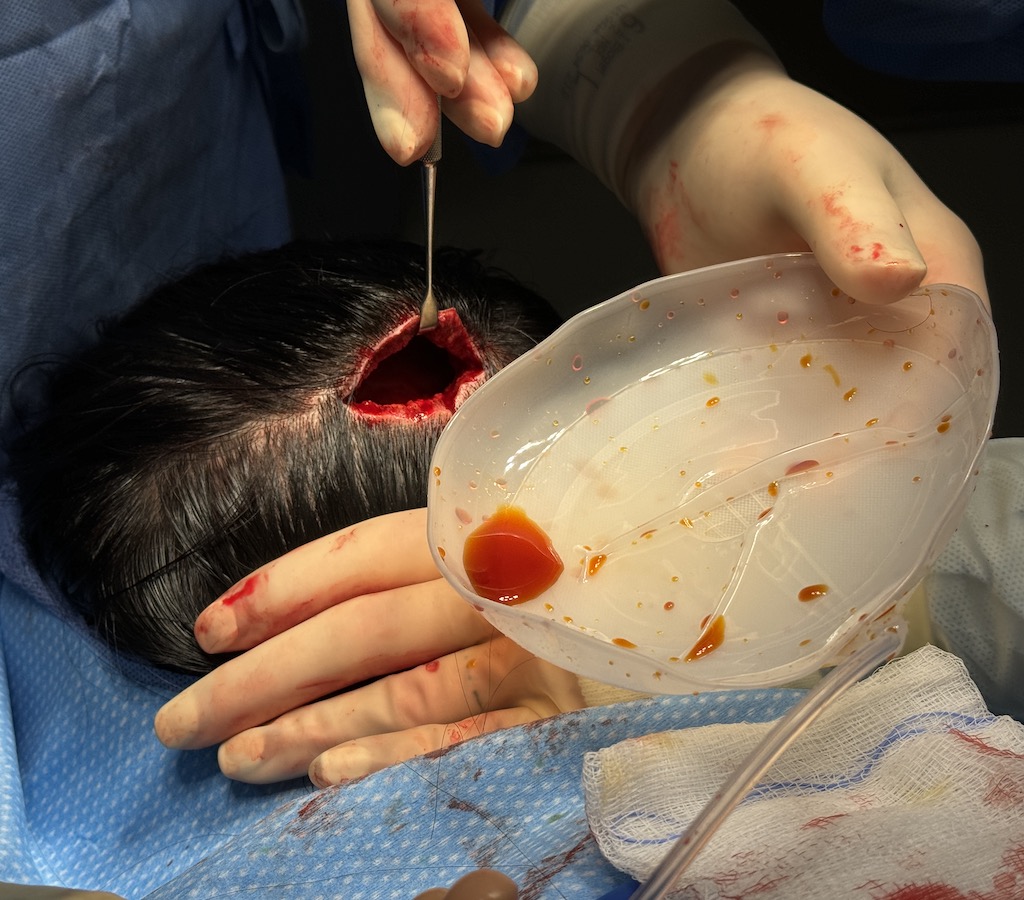

Desire for reduction of prominent occipital knob deformity.

Intraoperative result from occipital knob skull reduction through a direct small scalp incision.

Desire for reduction of prominent occipital knob deformity.

Intraoperative result from occipital knob skull reduction through a direct small scalp incision.